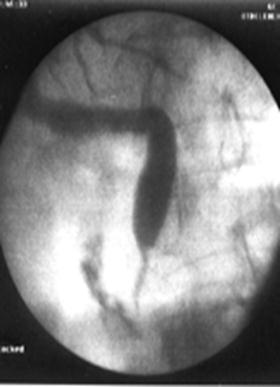

Рисунок 5 – А – дуоденоскоп; Б – канюляция БДС